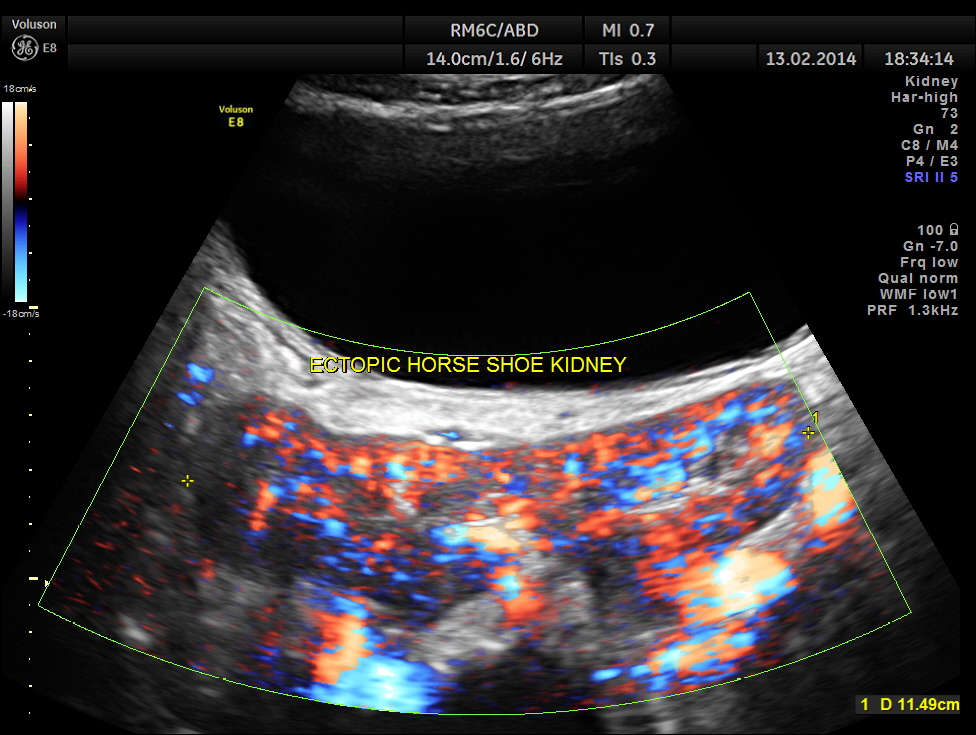

The following are the pictures of the kidney , which show the congenital horse shoe kidneys , placed ectopically in the pelvis. He had no urinary symptoms or low back ache at any time .

The power doppler pictures are given below.

Variant arterial supply Multiple, bilateral renal arteries Inferior mesenteric artery always crosses the isthmus Arteries arising from aorta or common iliac, internal iliac, external iliac or inferior mesenteric arteries

The lower poles of these kidneys fuse in the midline anterior to the aorta and spine. The isthmus is usually located at L4/5 level between the aorta and IMA.